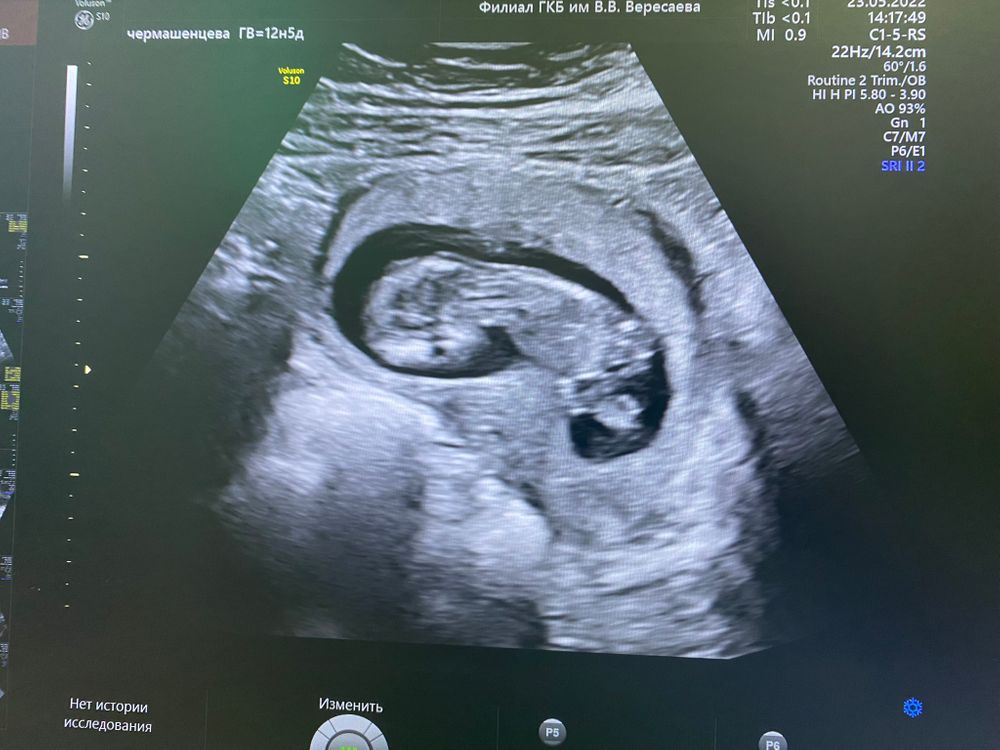

Первый скрининг, ничего не понятно, но очень интересно

УЗИ, КТГ, доплерНа днях у нас с ребетенком был первый скрининг на 12 и 5.

Глядя на фото все пытаюсь понять, где там ручки и ножки, но ничего не понимаю. А ещё положение не обычное, все вроде на спинке лежат, а тут космонавтики.

Врач сказала, что по узи все прекрасно, что конечно же радует.

Вы можете понять по фото где тут что ?

Ну он у вас боком лежит просто, видно голову, тельце, ножки. Ручки, наверное, вдоль тела, поэтому их на этом снимке не видно. Слева - голова, справа - ножки.